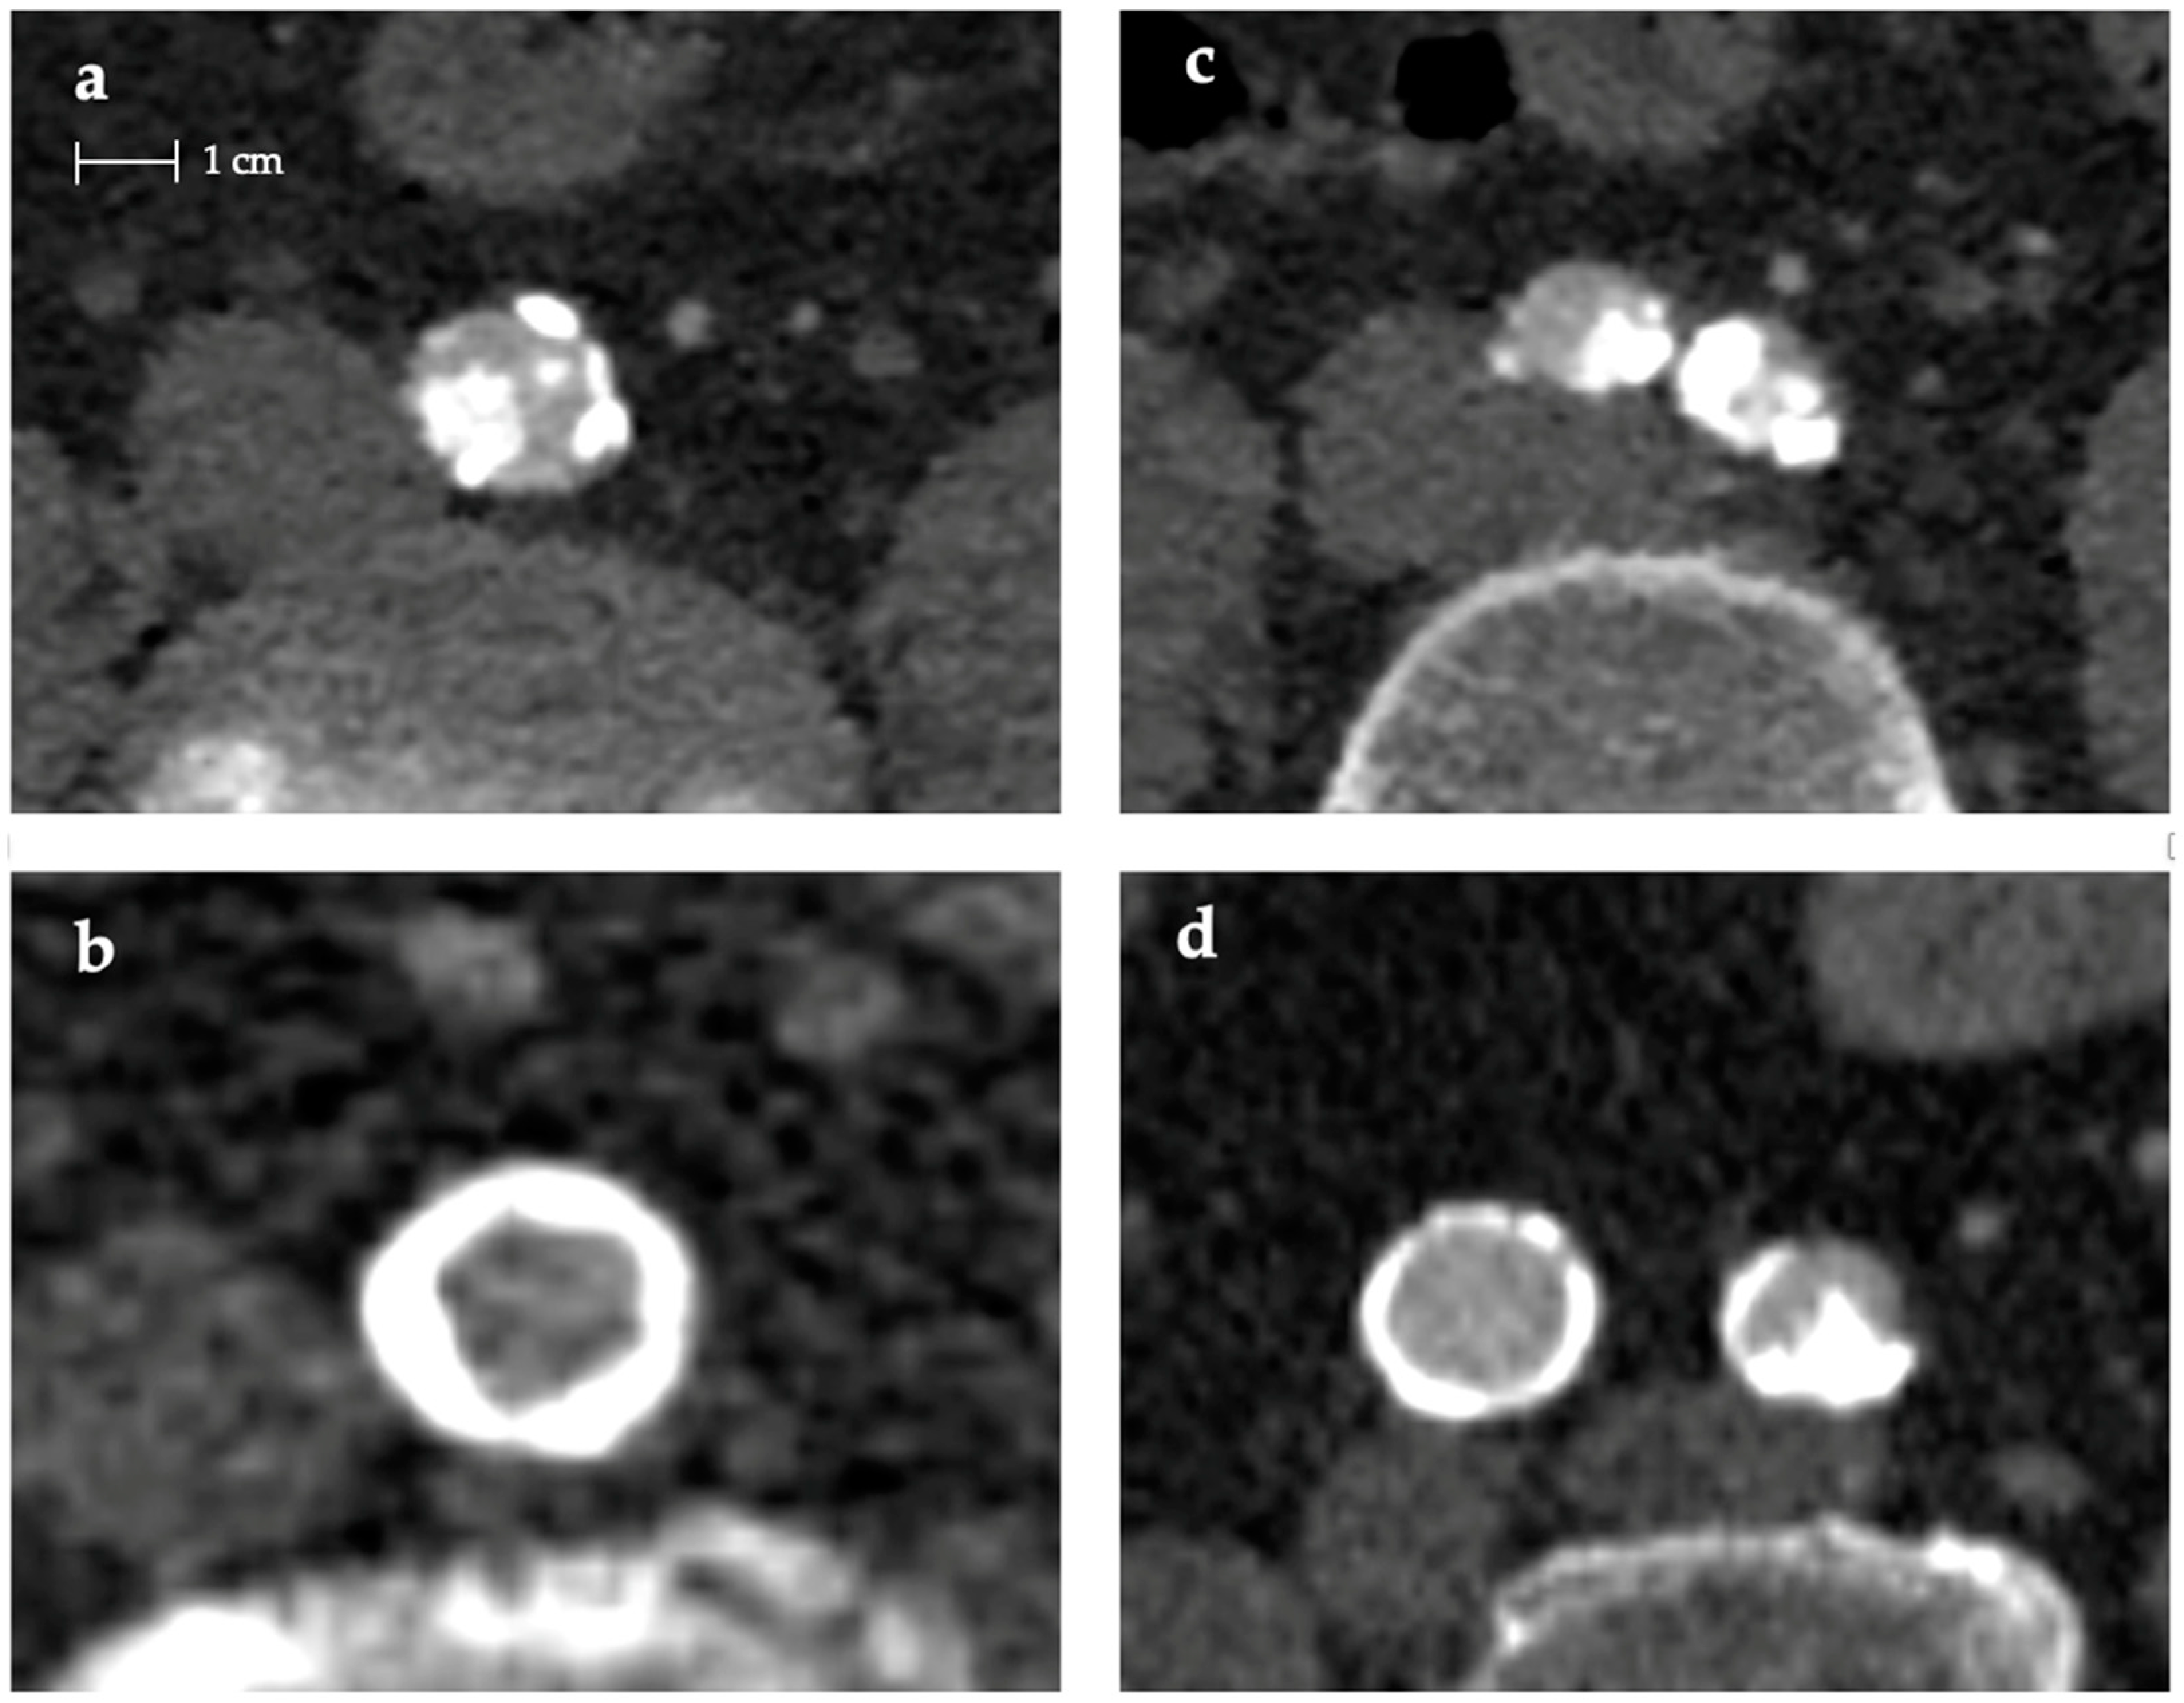

| Konijn et al. [14] Eur J Radiol 2020 | Retrospective | 204 | PET-CT | Manual | Abdominal aorta and lower limbs | Scoring characteristics: (1) severity: absent (no calcification), mild (1–3 small calcification), moderate (4–8 small or < 3 large calcifications), severe (>9 small or >3 large calcifications); (2) annularity: absent, dot(s), <90°, 90–270° or 270–360°; (3) thickness: absent, ≥1.5 mm or < 1.5 mm; (4) continuity: indistinguishable, irregular/patchy, or continuous. | Correlation between annular, thin, and continuous calcification characteristics and media calcifications while dot-like, thick, and patchy calcifications correlate to intima calcifications. |